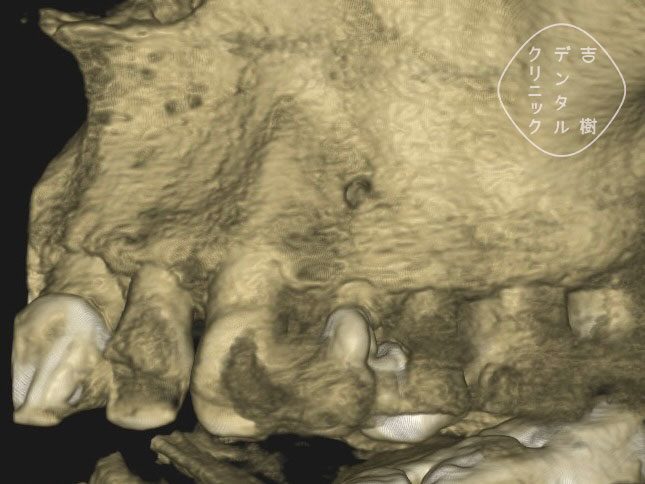

他院で抜歯と診断されたが、当院で根管治療を行い抜歯せずに治療できたケース。

根管治療を行う際には、まず、画像診断を行うことで歯の形状を確認します。通常、多くの歯科医院では「2次元」のレントゲンが使用されますが、この方法では初期の患部を見つけることが難しく、根管の複雑な形状を確実に把握するには不十分です。

そのため、当院では「3次元」の撮影が可能な「CT」を使用しています。CTはお口の周りを360度回転しながら撮影することで、レントゲンでは確認することができなかった細かい部分まで詳細に把握することができます。